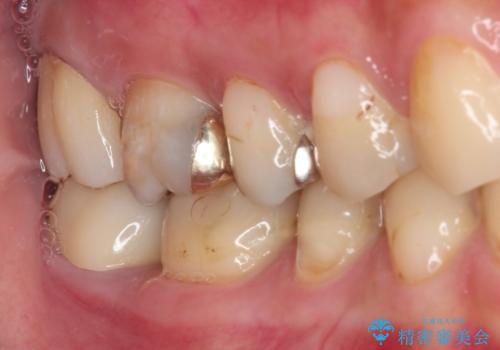

奥歯のむし歯が痛む セラミッククラウンとゴールドインレーによるむし歯治療